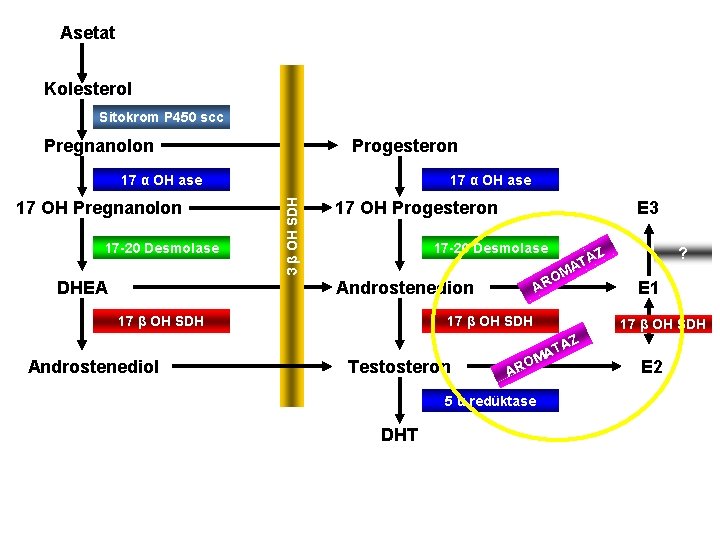

Asetat Kolesterol Sitokrom P 450 scc Progesteron Pregnanolon 17 OH Pregnanolon 17 -20 Desmolase 17 α OH ase 3 β OH SDH 17 α OH ase E 3 17 OH Progesteron 17 -20 Desmolase M O AR Androstenedion DHEA 17 β OH SDH ? Z A AT 17 β OH SDH E 1 17 β OH SDH AZ Androstenediol Testosteron O AR 5 α redüktase DHT T MA E 2